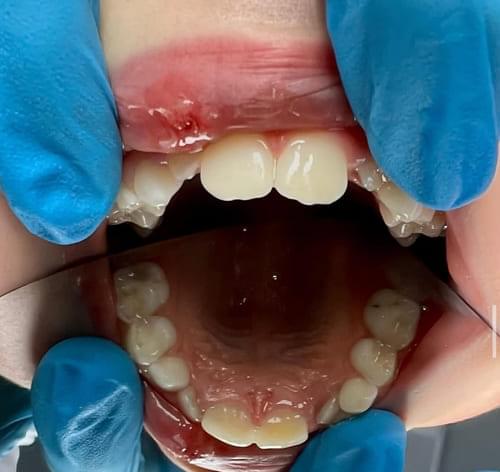

Дівчинка 2 років, але зуби вже мають глибокі ураження із залученням у запальний процес пульпи (“нерва”) зуба. На жаль, так трапляється і зволікати в такому випадку не можна. Було проведено лікування в умовах анестезіологічного забезпечення під контролем досвідченої анестезіологічної команди. Передні зубчики відновлено естетичними коронками, на жувальних зубчиках проведена герметизація фісур, а один вже має глибоке ураження карієсом, тому теж покритий коронкою. Одразу після лікування ясна можуть виглядати дещо травмованими, але за кілька днів вони повністю відновляться.